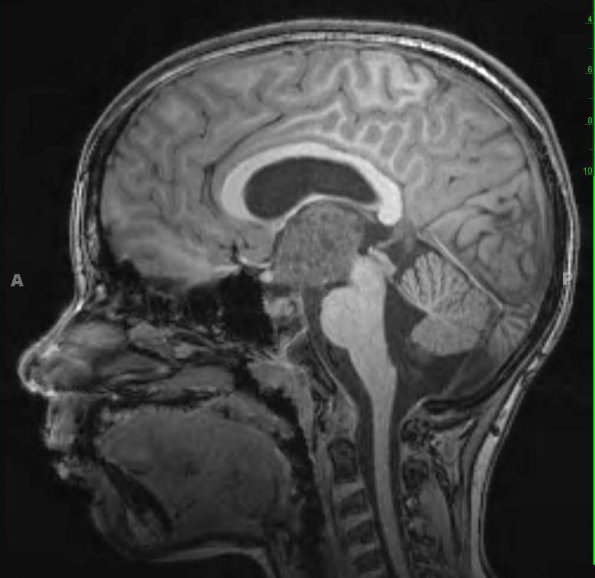

Case 38 ---- 11 year old male, III ventricle/hypothalamus ---- 38A1,2 MRI examination included T1 MPRAGE (38A1) and T2-weighted with contrast scans (38A2)